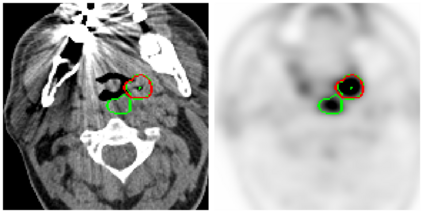

This paper presents an overview of the second edition of the HEad and neCK TumOR (HECKTOR) challenge, organized as a satellite event of the 24th International Conference on Medical Image Computing and Computer Assisted Intervention (MICCAI) 2021. The challenge is composed of three tasks related to the automatic analysis of PET/CT images for patients with Head and Neck cancer (H&N), focusing on the oropharynx region. Task 1 is the automatic segmentation of H&N primary Gross Tumor Volume (GTVt) in FDG-PET/CT images. Task 2 is the automatic prediction of Progression Free Survival (PFS) from the same FDG-PET/CT. Finally, Task 3 is the same as Task 2 with ground truth GTVt annotations provided to the participants. The data were collected from six centers for a total of 325 images, split into 224 training and 101 testing cases. The interest in the challenge was highlighted by the important participation with 103 registered teams and 448 result submissions. The best methods obtained a Dice Similarity Coefficient (DSC) of 0.7591 in the first task, and a Concordance index (C-index) of 0.7196 and 0.6978 in Tasks 2 and 3, respectively. In all tasks, simplicity of the approach was found to be key to ensure generalization performance. The comparison of the PFS prediction performance in Tasks 2 and 3 suggests that providing the GTVt contour was not crucial to achieve best results, which indicates that fully automatic methods can be used. This potentially obviates the need for GTVt contouring, opening avenues for reproducible and large scale radiomics studies including thousands potential subjects.